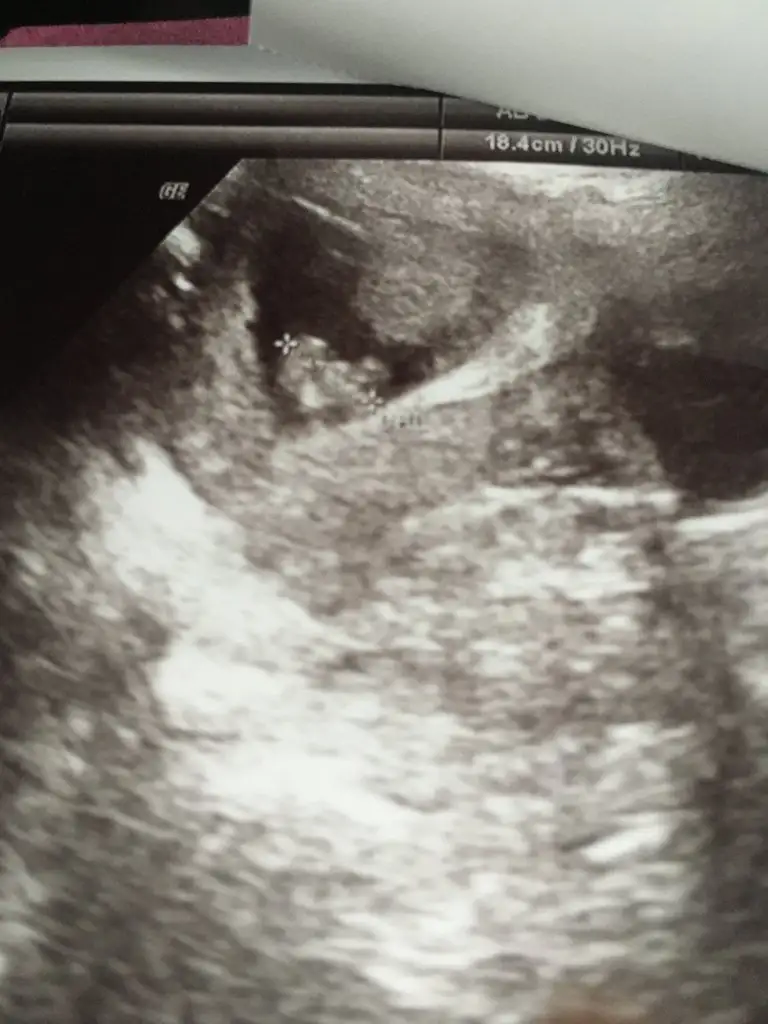

Yaaa benimkini de yorumlar mısınızzzz çok merak ettim

Eklentiler

• CADEFB2F-3AB7-40FD-A49B-14D9926058F8.webp

CADEFB2F-3AB7-40FD-A49B-14D9926058F8.webp

29,1 KB · Görüntüleme: 76